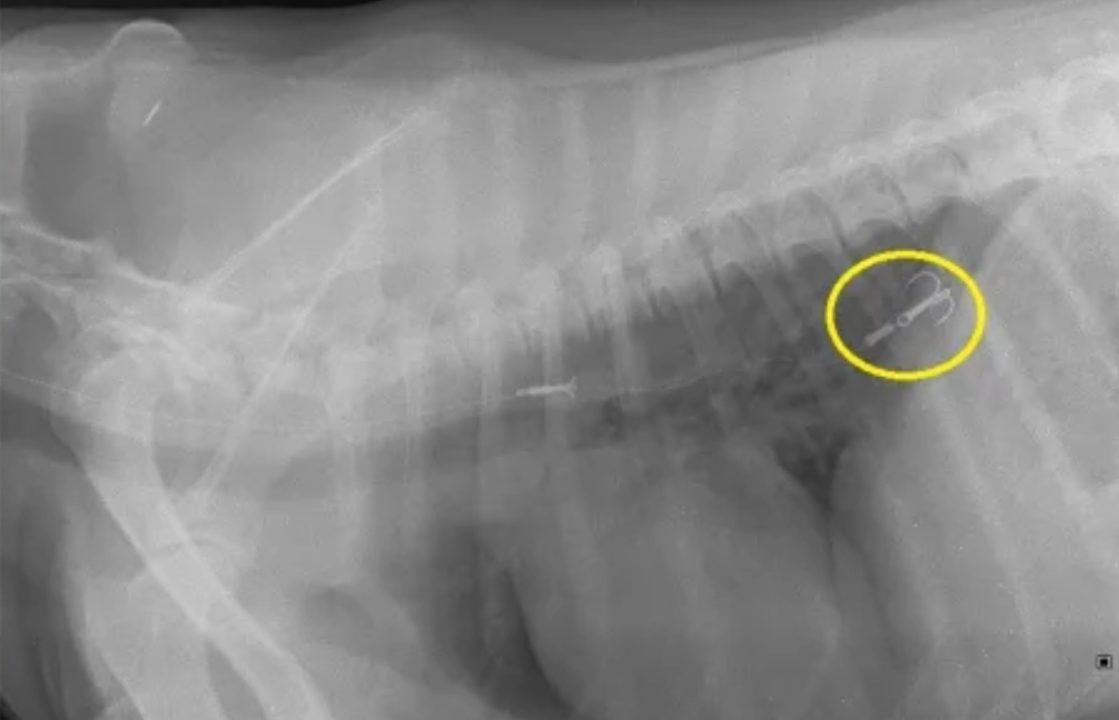

At the local vet, X-rays revealed the hook lodged in his oesophagus, and the dog was urgently referred to the Royal (Dick) Hospital for Small Animals, where it was found that the barb had travelled into Chip’s stomach.

University of Edinburgh via SuppliedBut the veterinary team were able to remove it using a protective cup attached to an endoscope, avoiding abdominal surgery. Chip was discharged the following day.